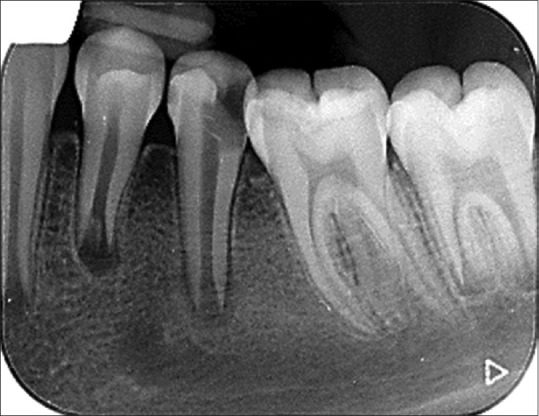

再生牙髓治疗是治疗牙尖开放坏死的一种权宜之计。再生牙髓治疗领域的临床研究取得了可喜的成果。本病例系列的主要目的是介绍再生牙髓治疗的影像学和临床表现。

Regenerative endodontics is an expedient therapeutic strategy for necrotic teeth with open apex. The promising result of clinical research in the regenerative endodontic treatment field is published. The main goal of this case series is to present the radiographic and clinical findings of the regenerative endodontic procedure.